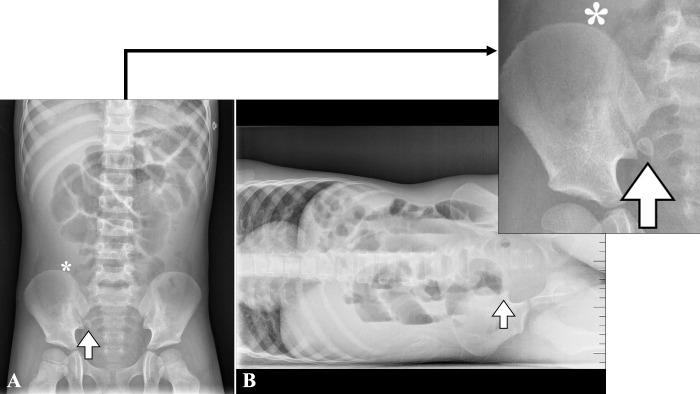

A 4-year-old male presented to the emergency department with fever, mucous diarrhea, abdominal pain, and vomiting for 36 hours. On abdominal palpation, he had generalized pain without rebound and increased hydroaereal sounds. The blood count showed leukocytosis and elevated C-reactive protein, and an ultrasound revealed intestinal loops with abundant content, increased peristalsis, and a normal appendix. Due to the suspicion of invasive gastroenteritis, he was admitted for observation. Due to the persistence of symptoms, a new ultrasound was performed which showed pelvic free fluid but did not identify the appendix. An abdominal radiography was previously performed, which showed an image compatible with appendicolith. With the suspicion of appendicitis, surgery was indicated, and an appendicular peritonitis was identified. The patient recovered well and was discharged seven days later. Diagnosing appendicitis in children can be a complex process. The most sensitive diagnostic tests are ultrasound and tomography. Abdominal radiography, however, is a widely available test with low radiation and has a positive predictive value of 90% for appendicitis (detecting appendicolith or periappendicular 'air silence'). In ambiguous cases, an abdominal X-ray could avoid invasive tests that require sedation or high doses of radiation.